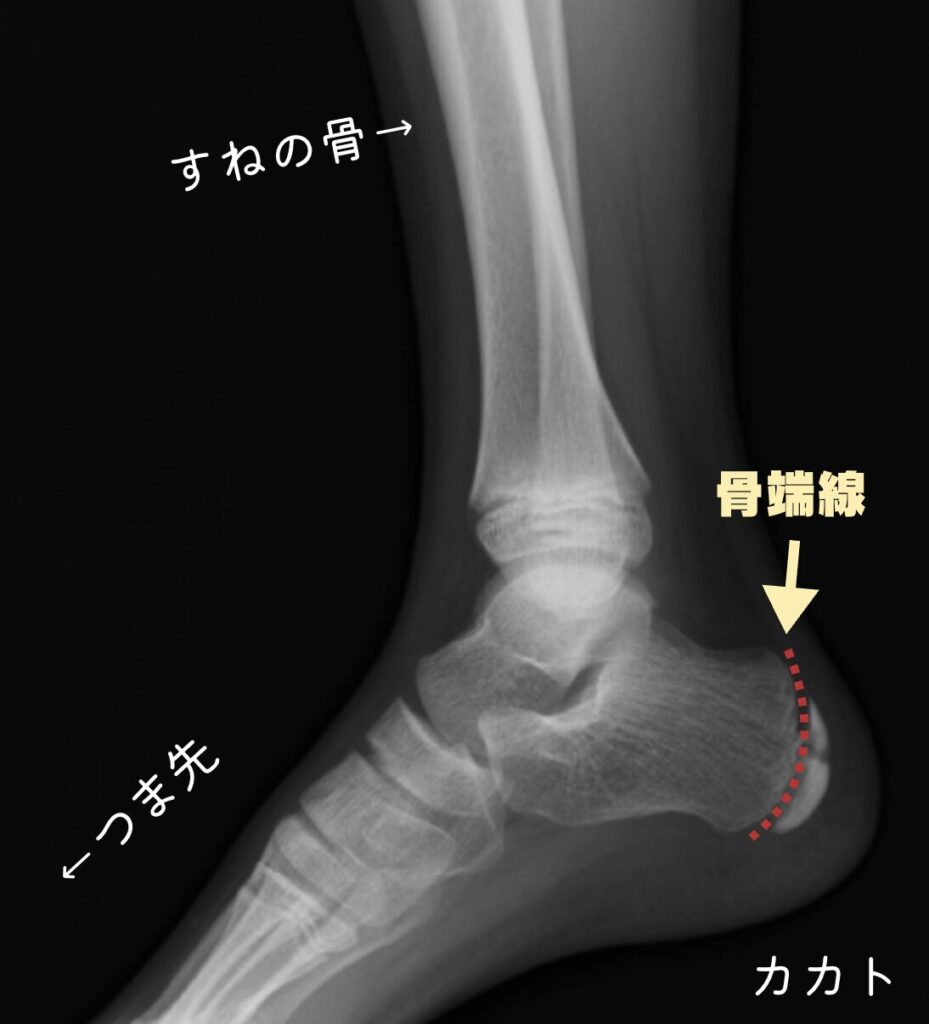

レントゲン写真ではこちらがわかりやすいかと思いますので引用させていただきます。

そして骨端線は赤い点線で示した場所になります

さて、カカトにはふくらはぎや足の裏の筋肉がつながっているのですが、その筋肉が使われすぎてカカトの骨をグイグイと引っ張ってしまったらどうなるでしょうか?

骨端線はとても弱い部位ですので、左の図のように筋肉に引っ張られてしまうと、上下どちらかにズレてしまったり、場合によっては上下に割れてしまったりしそうですよね。

(引用させていただいたカカトの骨は実際に上下に割れているのがわかります)